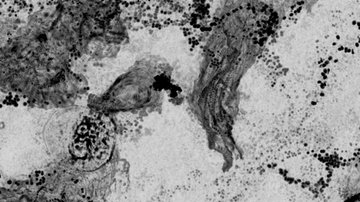

Aktuality — 11.05.2021 Experti dokážou ovlivnit hojení ran spojením krevních destiček a kmenových buněk